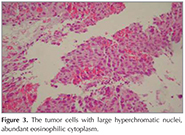

?A 43-year old male patient was admitted with dyspnea and chest pain. On physical examination the breath sounds were markedly diminished at right hemithorax and he had bilateral gynaecomastia. He was a smoker and his smoking history was 22 pack years. A chest radiograph showed opacity involving all zones of right hemithorax and nodular opacities at left hemithorax (Figure 1). A thorax computed tomography (CT) revealed a mass lesion occupying almost all right hemithorax and multiple masses in the left hemithorax. There was also pleural effusion and compression atelectasis at right hemithorax. Laboratory studies revealed a normal complete blood count and serum biochemistry. The erythrocyte sedimentation rate was elevated. Since he was a young patient, had bilateral multiple masses at thorax CT and also had gynaecomastia, a germ cell tumor was suspected and serum β-HCG level was analyzed. The serum β-HCG level was found as elevated: 4261 mIU/mL (normal less then 2.0). Positron emission tomography (PET)-CT revealed pathologic 18 FDG uptake at mass lesions in both hemithorax and mediastinal lymph nodes (Figure 2). Positron emission tomography and ultrasonography showed no gonadal involvement. A bronchoscopy was performed and an endobronchial lesion at the apical segment of right upper lobe was observed. A definitive diagnosis was not achieved by pathologic examination of biopsy specimen, bronchoscopy was repeated and samples were taken by cryobiopsy. Tumor consisted of solid sheets of uniform large tumor cells (Figure 3). Tumor cells were positive with P63 and β-HCG (Figure 4). Keratin 5/6, TTF-1, PLAP and AFP were negative in tumor cells. Mucine carmin staining was negative. We didn't observe syncytiotrophoblast and cytotrophoblast. Our case was β-HCG secreting nonsmall cell lung carcinoma. Since the patient was inoperable, a chemotherapy protocol was started.